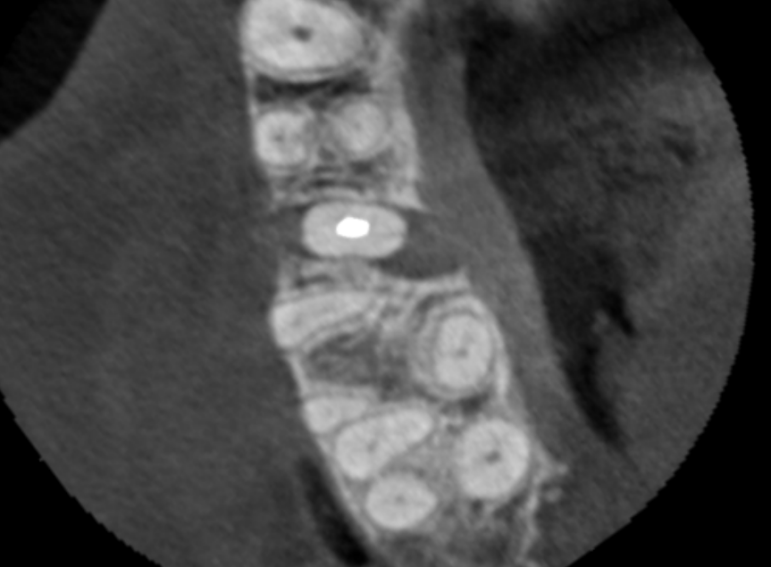

Case 24 – Endodontics

Transillumination after trauma